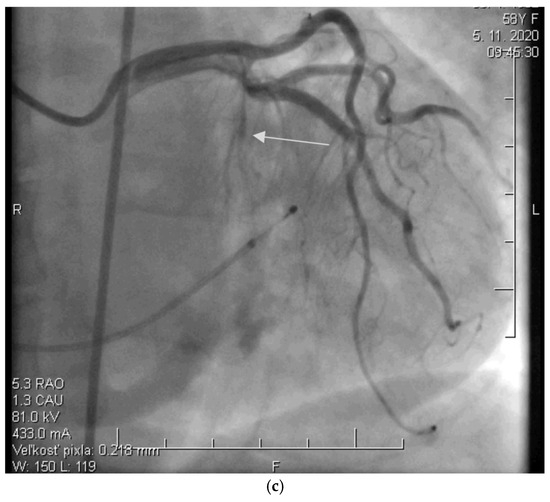

Before the procedure, a temporary pacemaker was inserted into the RV via a venous approach to prevent potential periprocedural conduction disorders. After the pacemaker was placed, selective injection of the left coronary artery was performed via a transfemoral approach to assess the anatomy of its branches (Figure 2a). Using a pigtail catheter introduced into the LV, the pressure gradient between the LV apex and the aorta was measured at rest and after provocation with a ventricular extrasystole, Valsalva maneuver, or, less frequently, nitrate administration.

Figure 2.

(a) Angiographic image of the left coronary artery showing a septal branch (arrow) (photo and copyright: T.P.). (b) Administration of 96% alcohol into the septal branch using an over-the-wire (OTW) balloon catheter (photo and copyright: T.P.). (c) Final effect of ASA with Closure of the Septal Branch (photo and copyright: T.P.).

Subsequently, a specialized over-the-wire balloon catheter was inserted into the septal branch supplying the area contributing to the LVOT narrowing (most commonly the basal interventricular septum. The balloon catheter was inflated to occlude the lumen of this vessel, followed by the injection of an echocontrast agent and echocardiographic assessment of the perfusion area and localization of the selected septal branch (echo-guided approach). After identifying the appropriate septal branch, 96% alcohol in a volume of 2 mL was administered uniformly to all patients according to internal protocol (Figure 2b).

Ten minutes after the alcohol application, the balloon was deflated, and the residual pressure gradient between the LV apex and the aorta was measured at rest and after the aforementioned provocative maneuvers. To conclude the procedure, a selective injection of the LCA was performed to confirm the ablation of the septal branch and exclude potential alcohol leakage into other parts of the coronary circulation, which could cause the no-reflow phenomenon (Figure 2c).